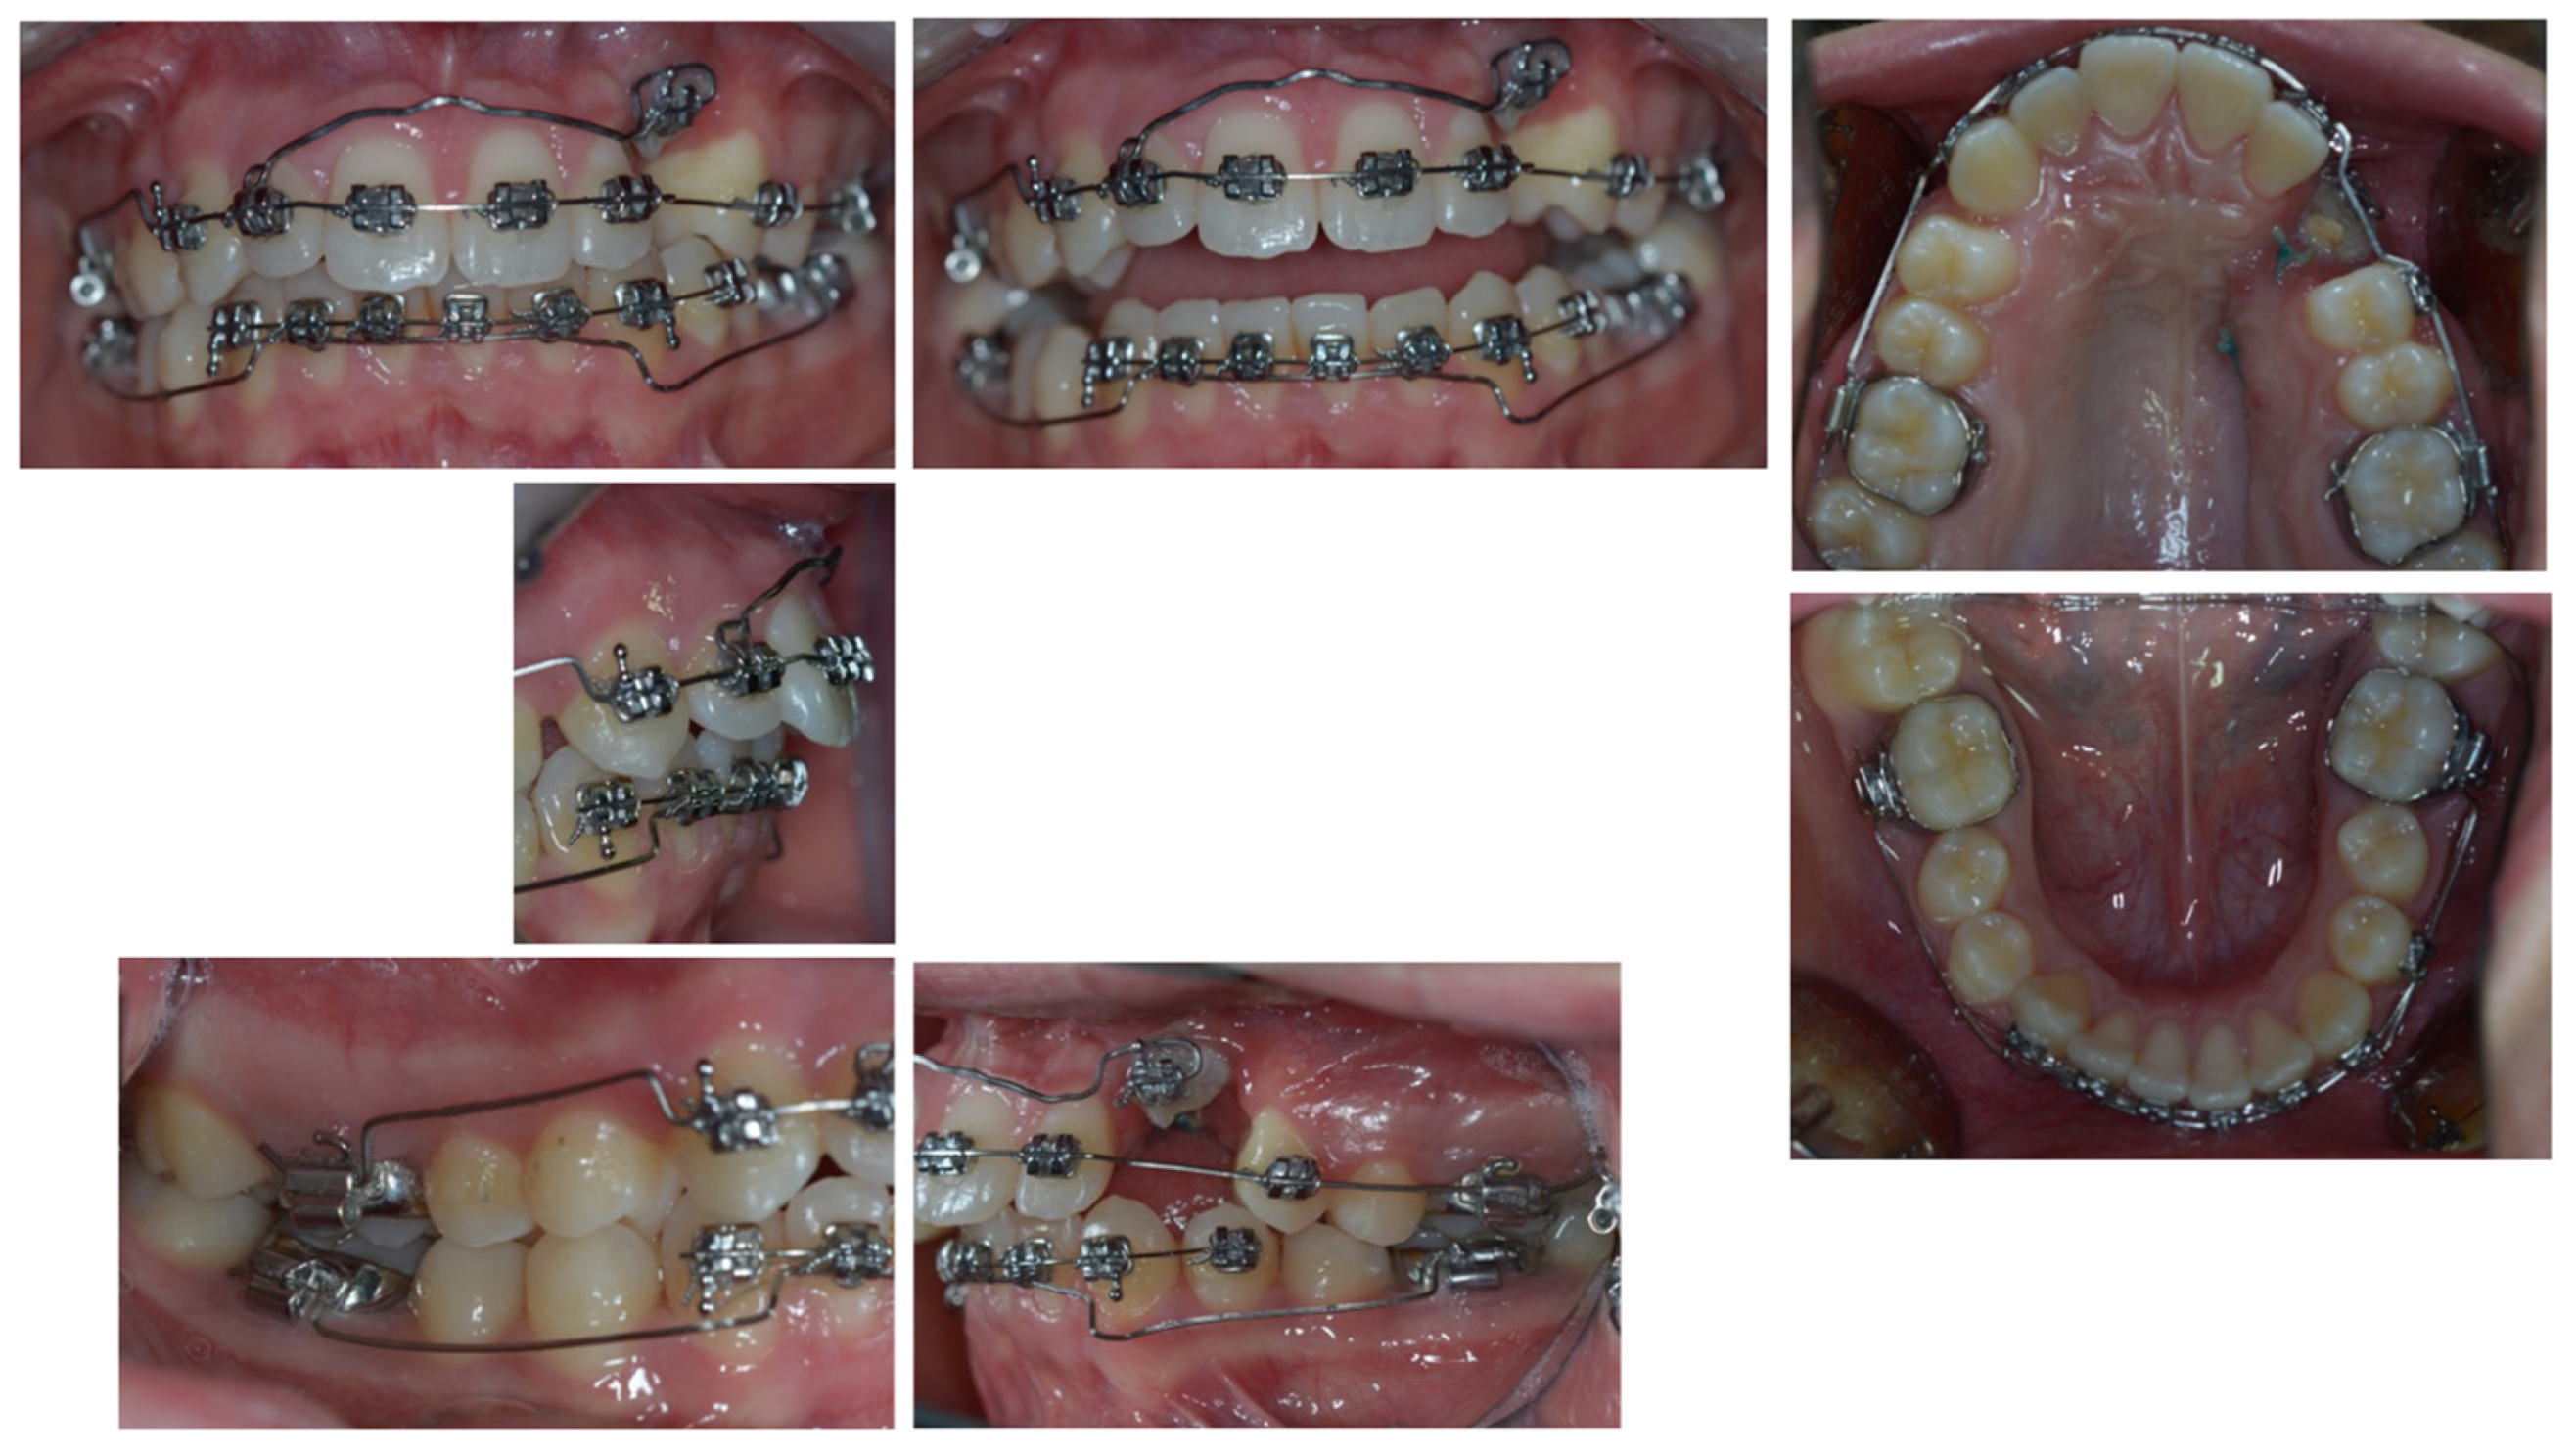

3. Therapeutic Interventions

4. Follow-Up and Outcomes